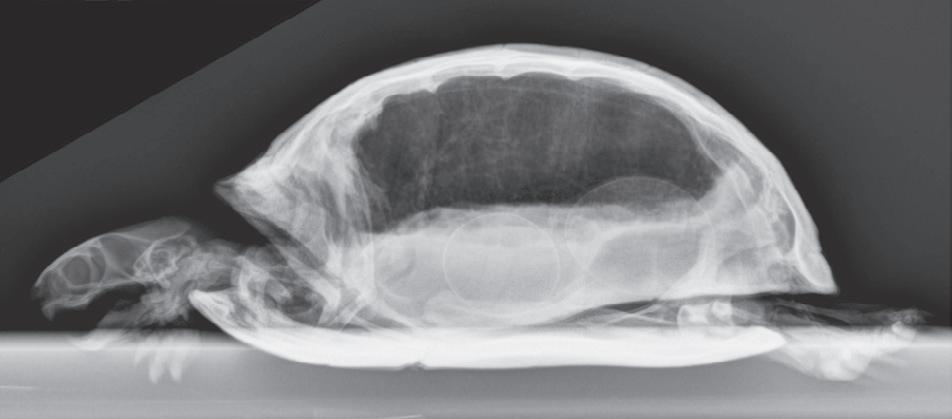

Figure 1-6. Dorsoventral (A), lateral (B), and rostrocaudal (C) radiographs of a box turtle. In A and B, which are orthogonal to each other, it is clear that the subject is a turtle. Eggs are visible in the coelom. In C, which is also an orthogonal view with respect to both A and B, it is not obvious that the subject is a turtle because this orientation is uncommon and unfamiliar. The eggs are also not visible in C.